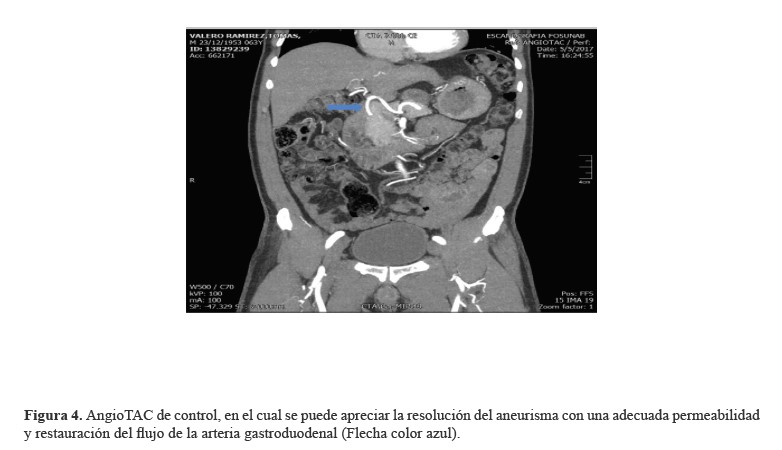

Se decidió intervenir al paciente con manejo endovascular con coils, realizando una punción en la arteria braquial derecha. Posteriormente, se ejecuta aortograma y se identifica el tronco celíaco. A continuación, se efectúa cateterismo supraselectivo de la arteria gastroduodenal y se realiza angiografía, que muestra sangrado activo de aneurisma sacular de la arteria gastroduodenal, con extravasación del medio de contraste. Inmediatamente, se cateteriza el aneurisma y se emboliza con coils; así, se logra el manejo del sangrado y una adecuada tolerancia del paciente al procedimiento. En control angiográfico, se observó exclusión total de AAG con flujo escaso distal y, en aortograma abdominal, se identificó aorta abdominal normal (Figuras1-4).

Figura 4.AngioTAC de control, en el cual se puede apreciar la resolución del aneurisma con una adecuada permeabilidad y restauración del flujo de la arteria gastroduodenal (Flecha color azul).